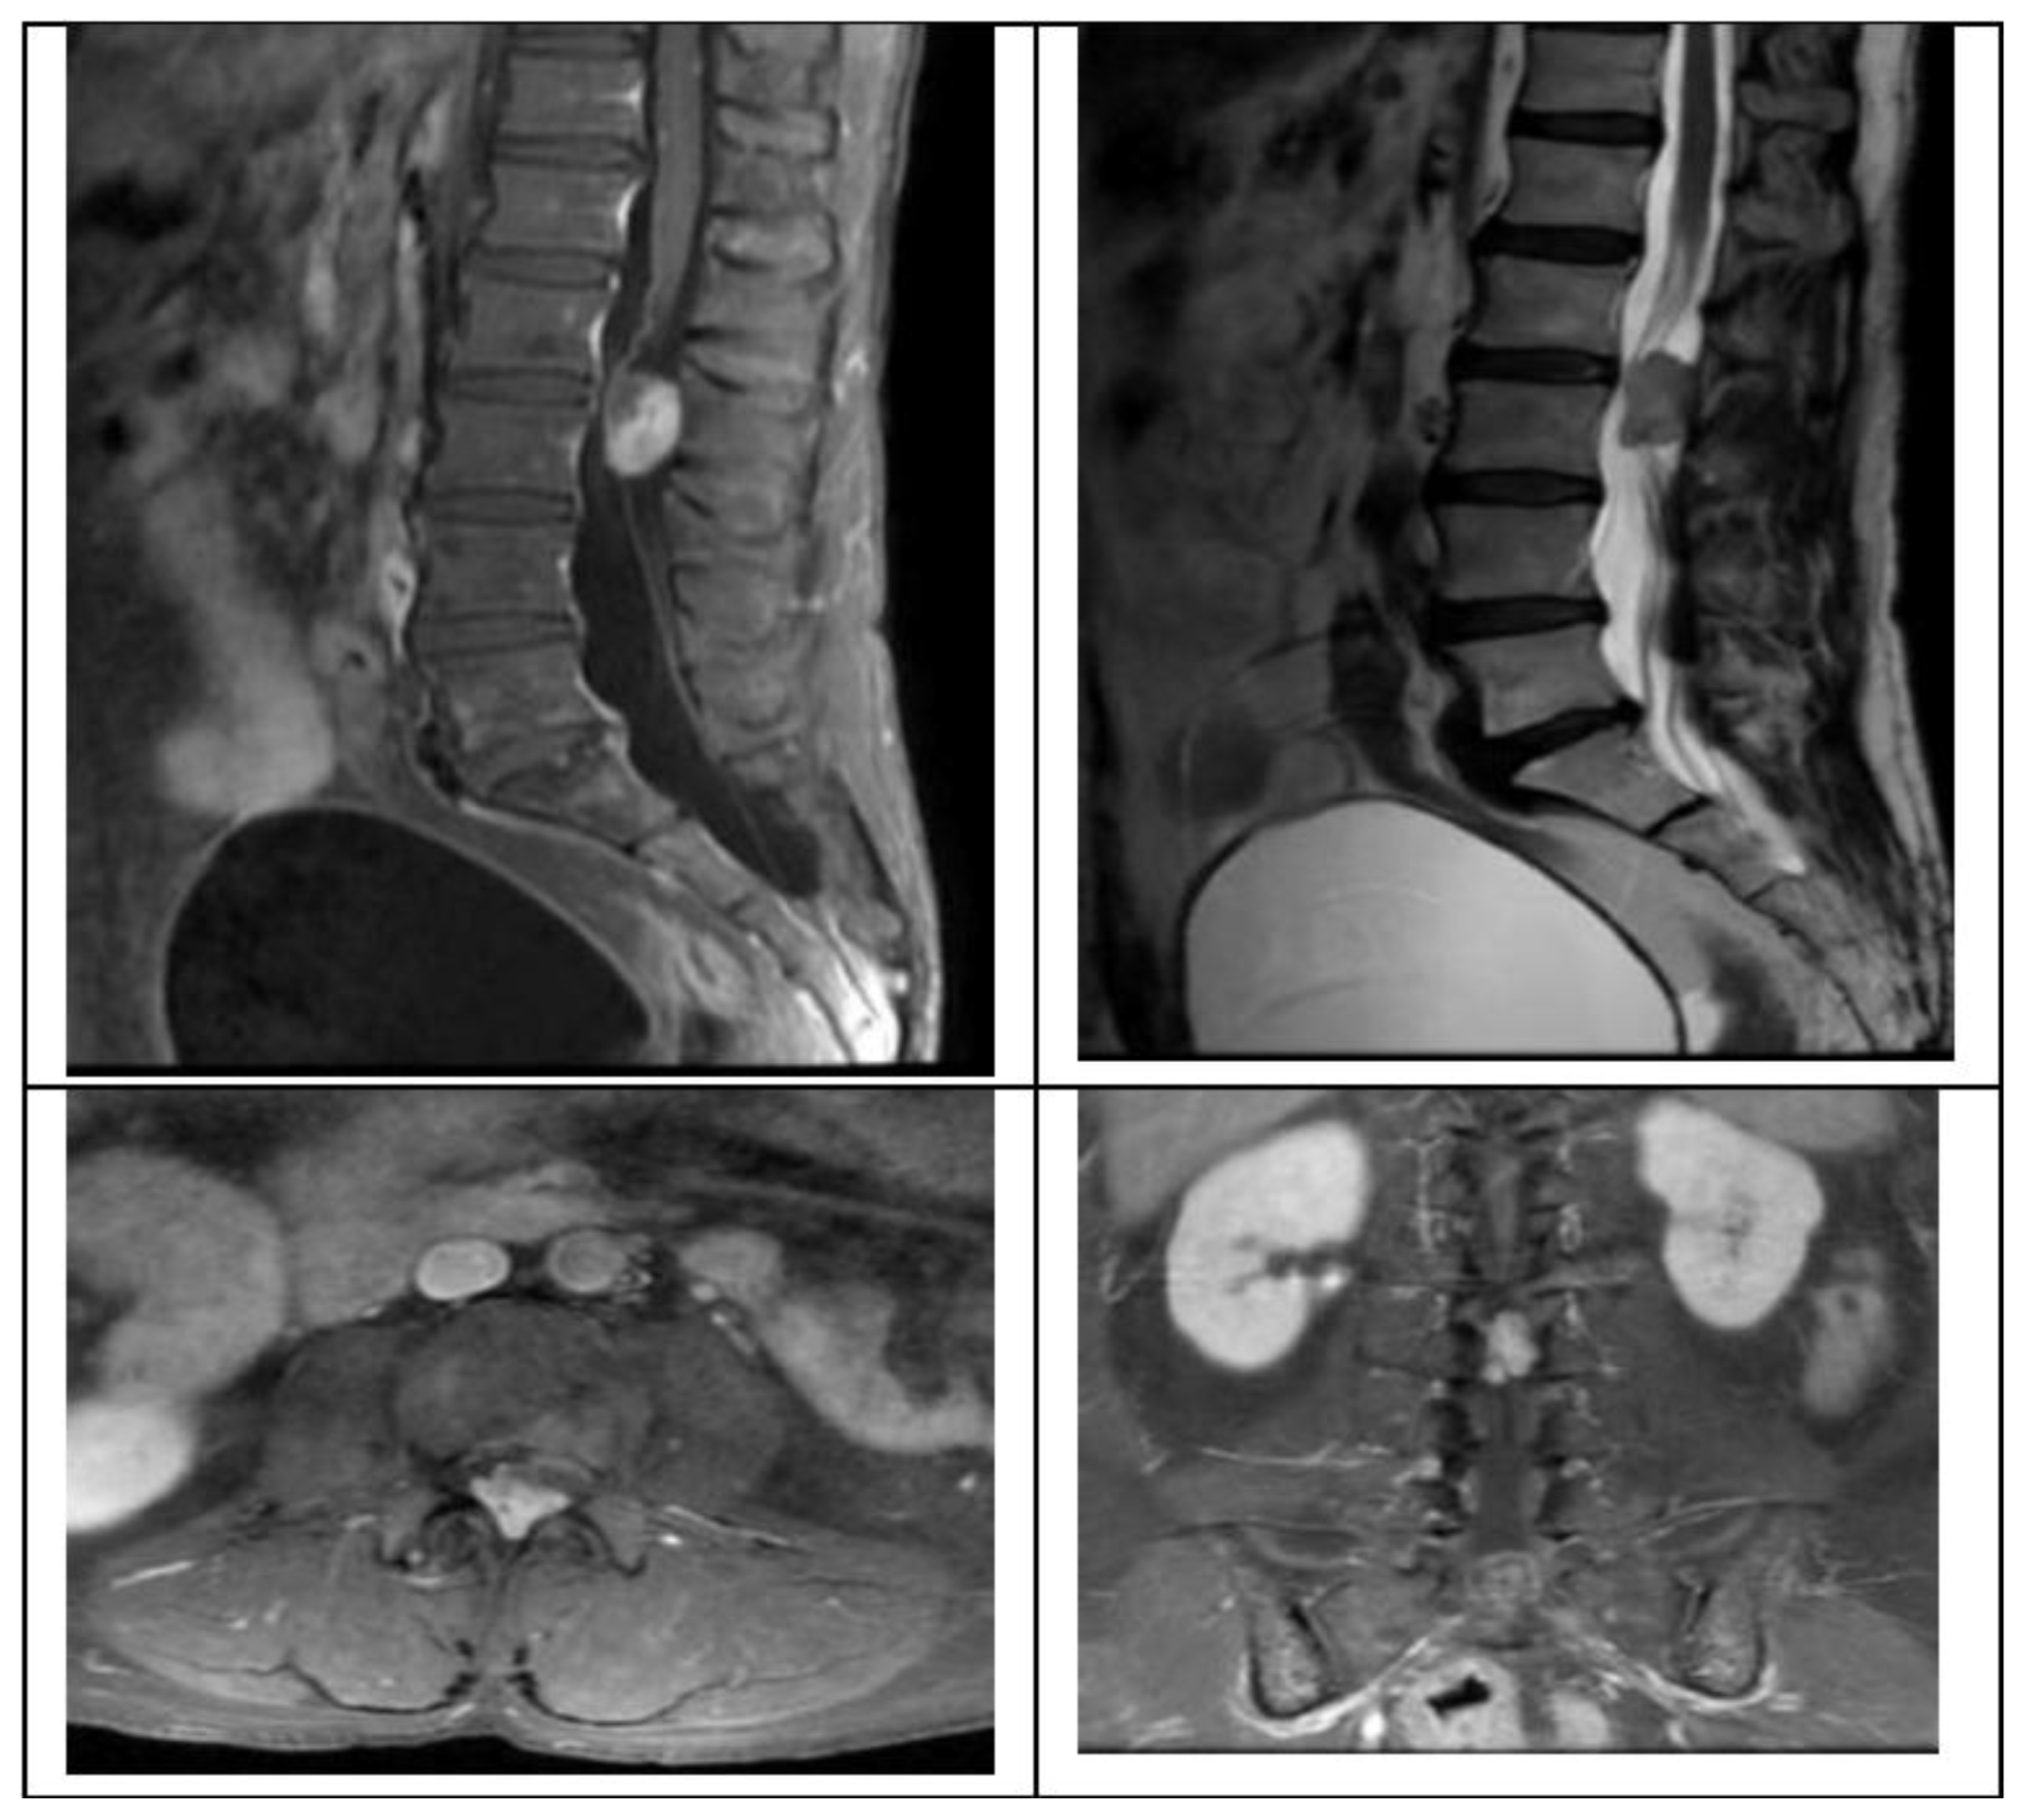

We present the case of a 58-year-old female with 2 months of progressive left leg radiculopathy with a leg VAS 9/10, low back pain, back VAS 7/10, and weakness in both lower limbs, with gait impossibility, and neurogenic bladder, MRI revealed a L2-L3 intradural extramedullary lesion that occupies 80% of the spinal canal (Figure 1), as previously described we plan are surgery with UBE technique, with a right side approach, with the spinometric landmarks (Figure 2), with minimal muscular tissue disruption, with bilateral laminotomy of the cephalic and caudal lamina with wider O-cut with over the top technique and flavectomy with Kerrison’s rongeur and curettes, we do a mid-line durotomy with a single cut with 11 blade scalpel and wide de incision with Rhoton dissector, visualize the tumor and perform the dissection with Rhotons and Penfield’s, water dissection increasing the pump flow and then extract the lesion with pituitary forceps without complications over the procedure. We perform closure with a 6-0 prolene suture with the previously described technique. (Figure 3)

Figure 1. MRI showing intradural extramedullary l2-l3 lesion.